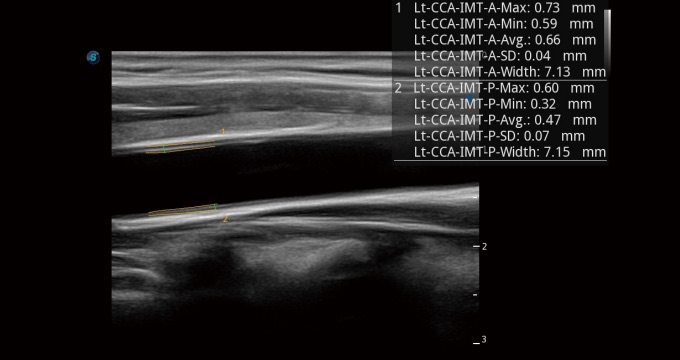

Single crystal transducers greatly improve signal ratio, acquire stunning images and provide superior sensitivity and resolution for both the near and far fields, by increasing the uniformity of crystal alignment and raising energy transmission efficiency. Single crystal C1-5 for abdominal and OB patients and S1-5 for cardiology and transcranial applications. Composite crystal linear transducers, by reforming the conventional piezoelectric materials, achieve a better acoustic spectrum and lower acoustic impedance to serve well in vascular, breast, thyroid, MSK, etc. The combo of 12L-A, 12L-B, 9L-A covers an ultra-wide frequency bandwidth, leaving nearly no blind spot for all sorts of scanning.